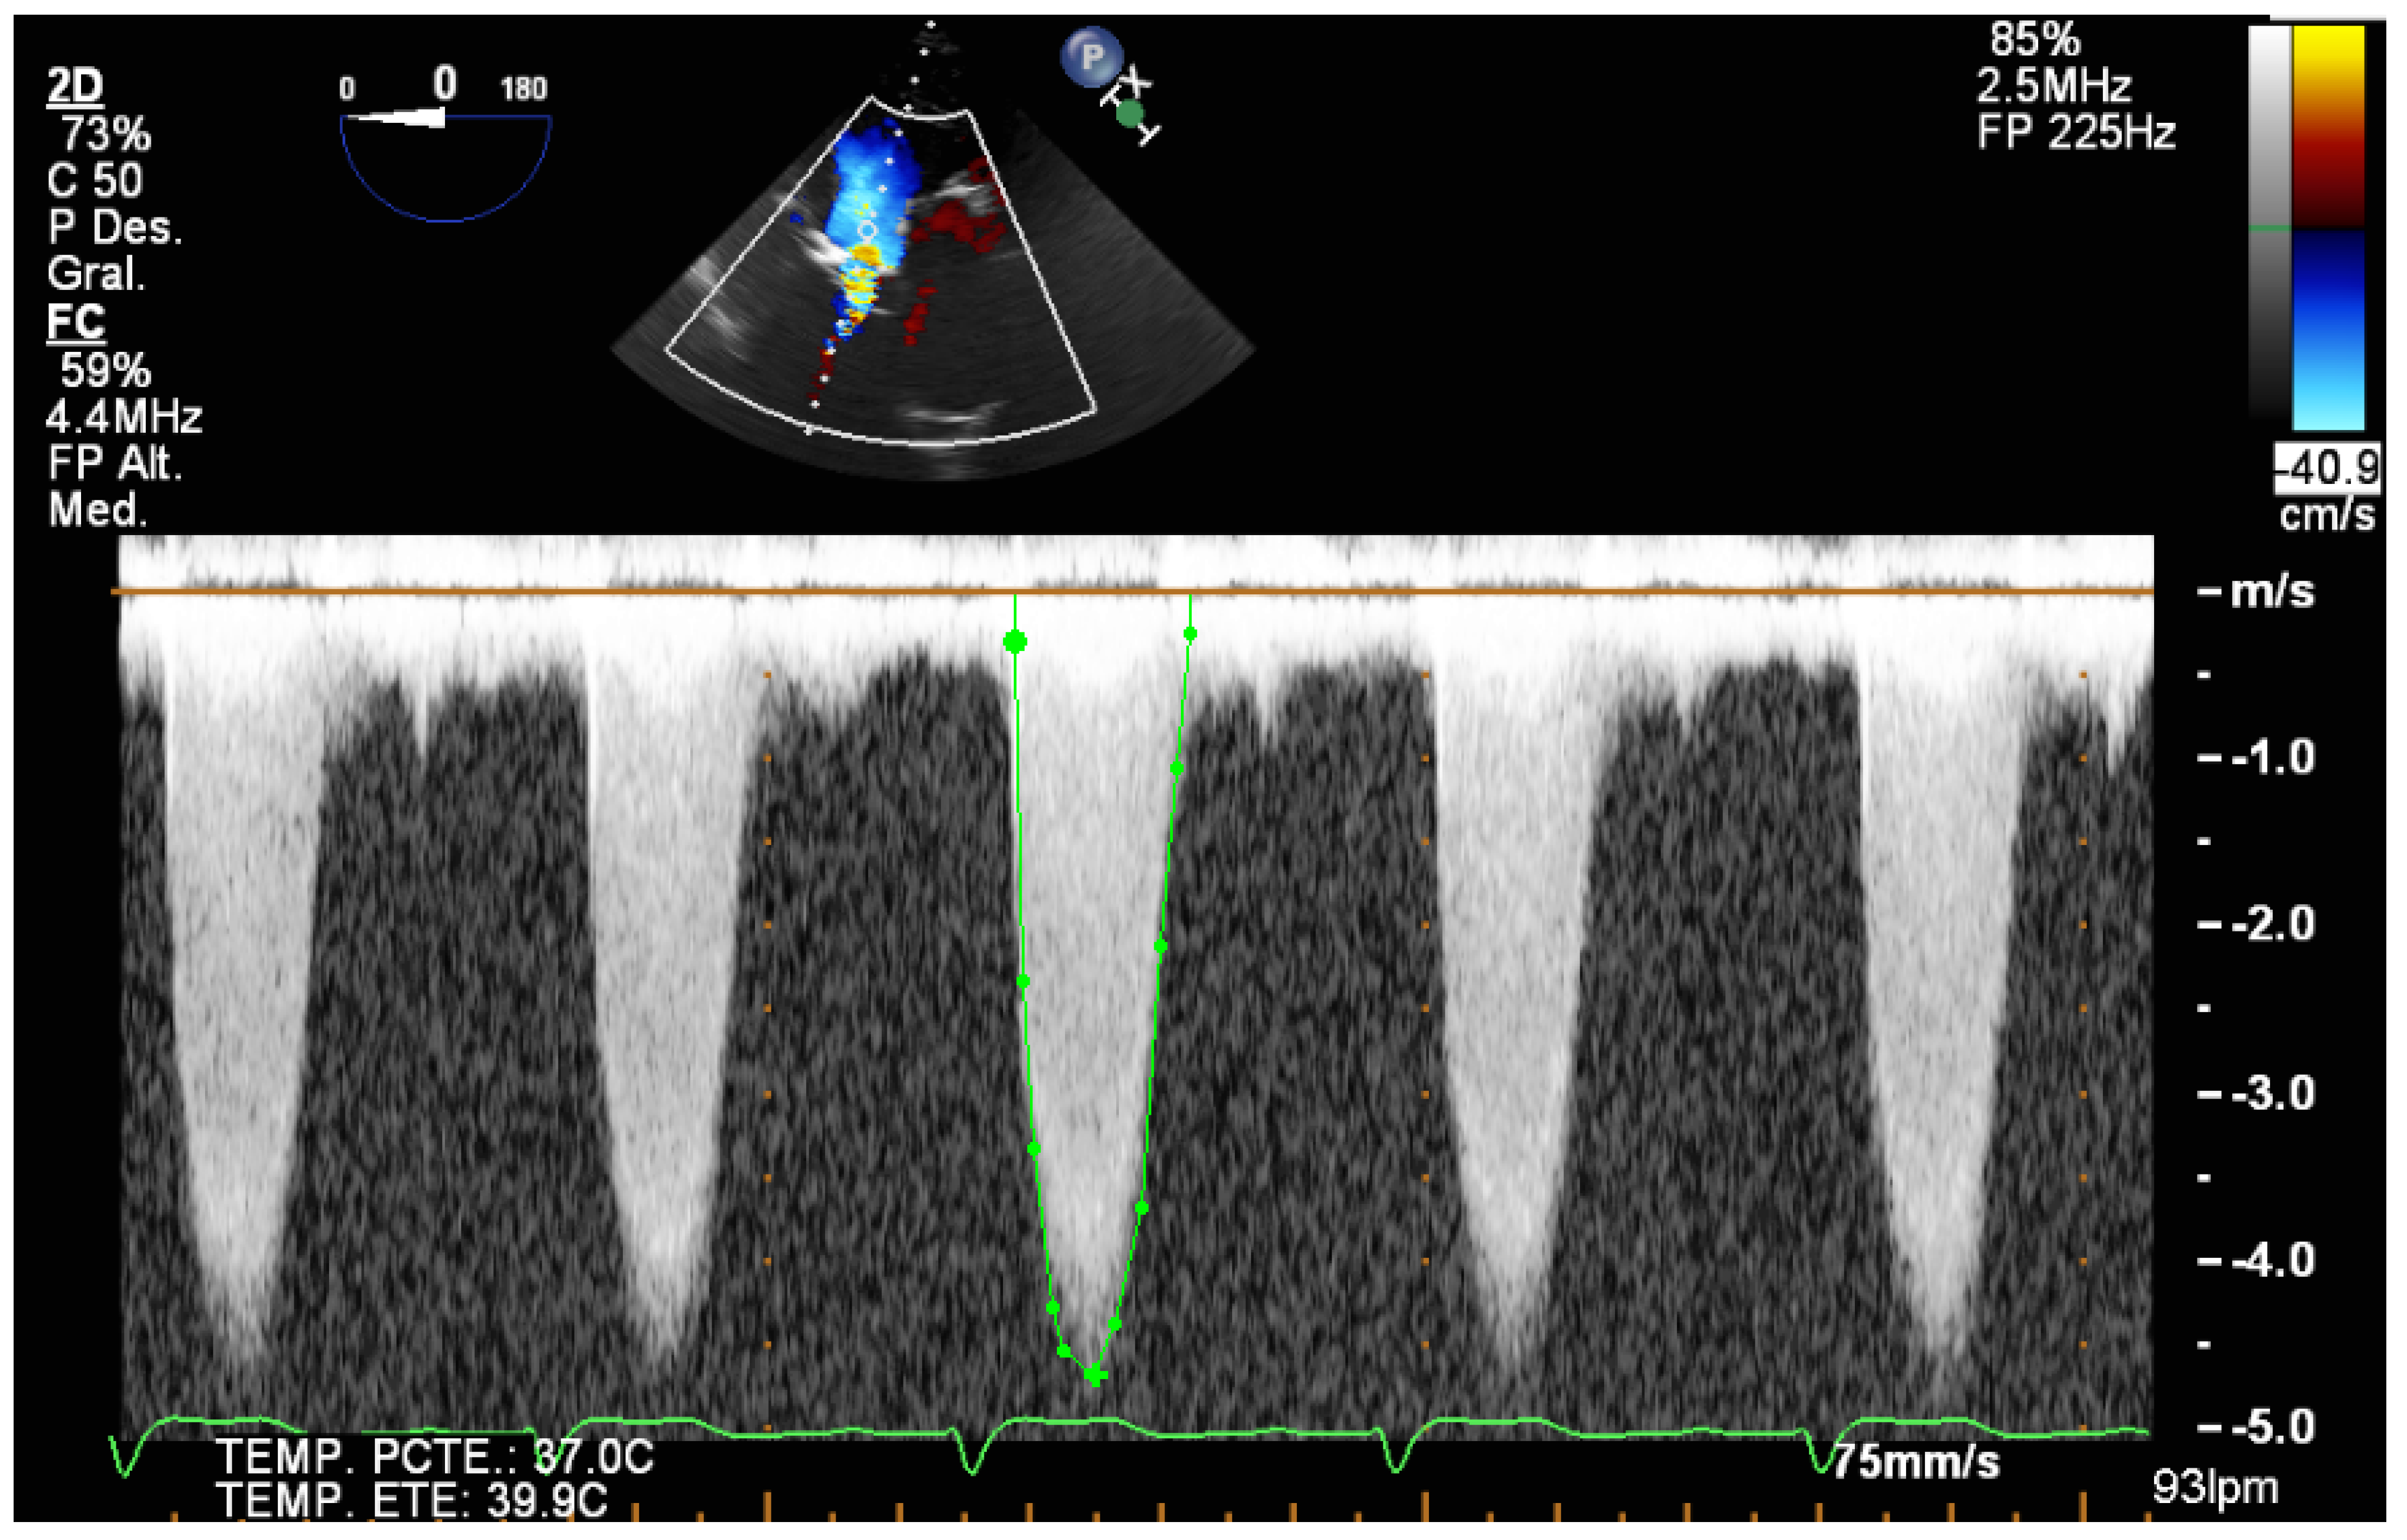

| 2 | TEE monitoring during TAVR implantation allows us to properly position the valve in the aortic annulus, avoiding positioning errors and possible migrations of the prosthesis. |

| 3 | Three-dimensional TEE is the best technique to detect and quantify perivalvular regurgitation after TAVR implantation, a fundamental aspect in deciding whether immediate valve postdilation is needed or not. |